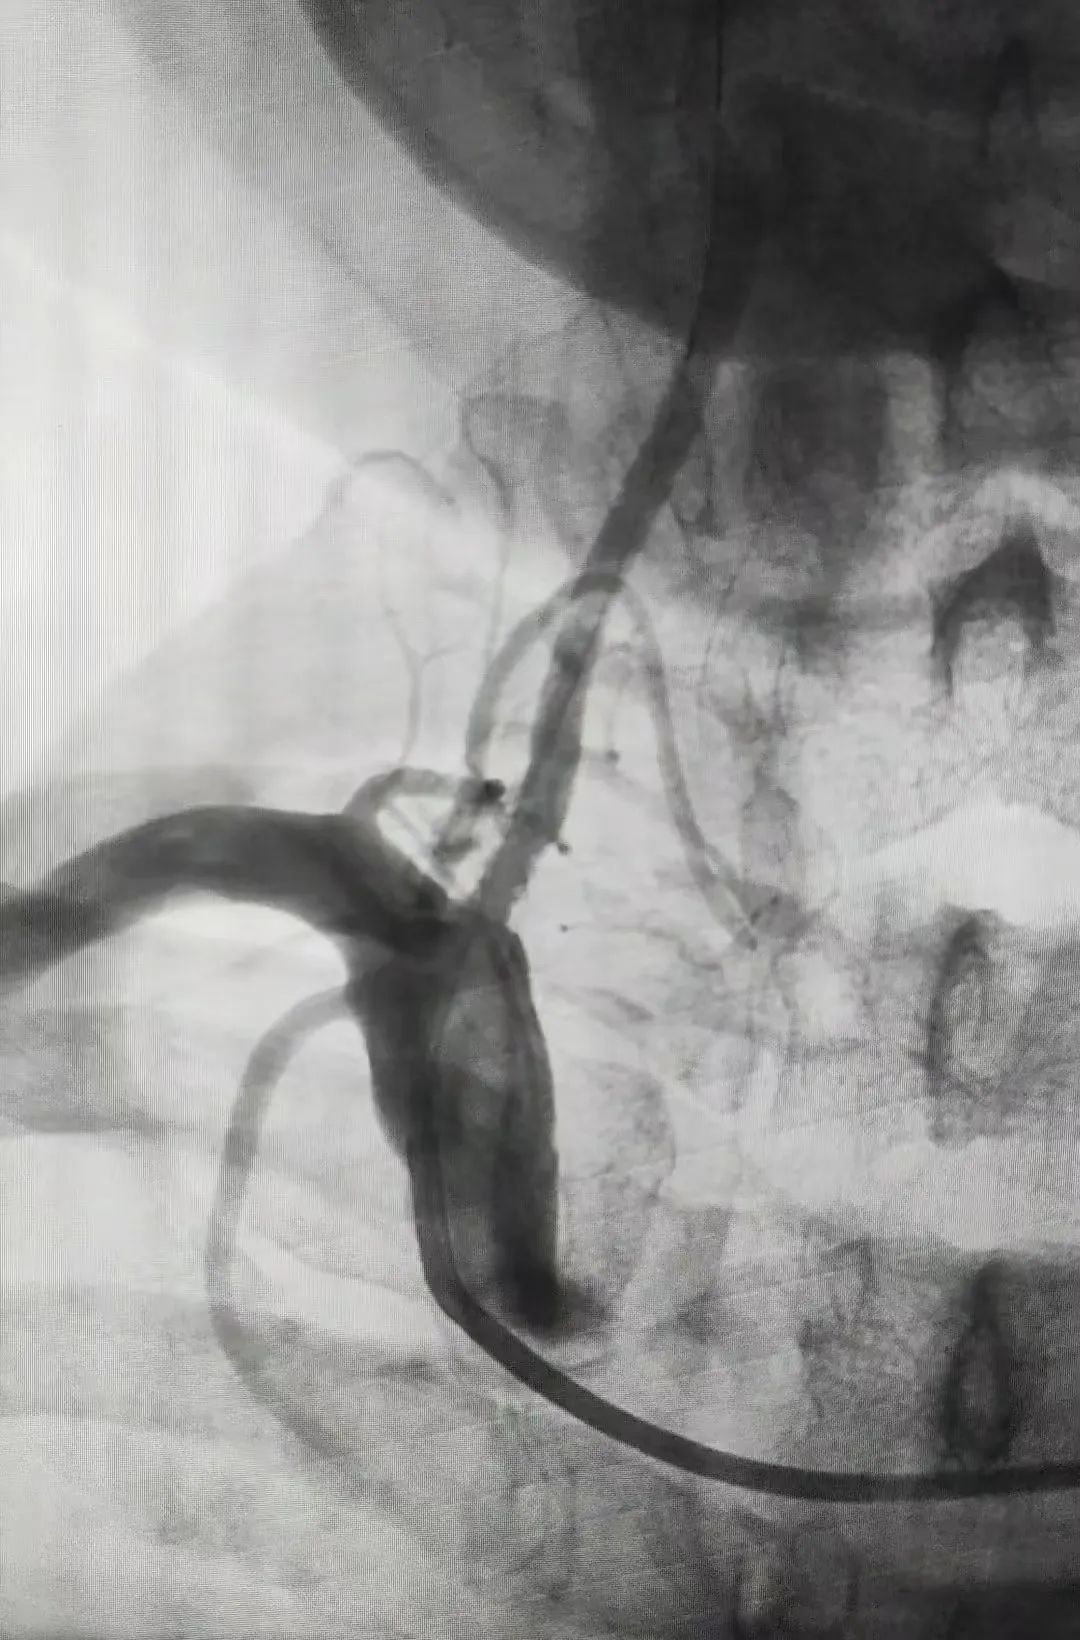

术后右椎动脉成形良好

整个术程迅速且顺利,术后造影证实支架位置良好,打开完全,狭窄解除,血流通畅。术后第二日患者诉头晕明显改善,双眼都较术前明亮了许多,未诉其他特殊不适,能下床活动。患者和家属都非常高兴,由衷地向平谷区中医医院神经外科介入医护团队表示感谢。